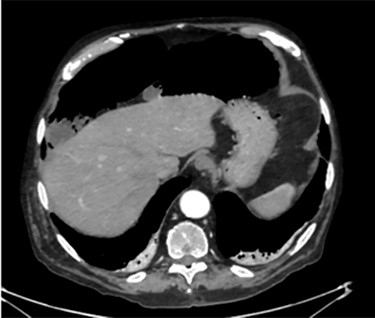

This is a case of a 79-year-old man who underwent contrast-enhanced Brain-CT for loss of consciousness. Past medical history included diverticular disease, COPD, hypertension, atrial fibrillation and appendectomy. Of note, he had no prior history of endoscopic procedures or recent trauma. The CT showed a primary cerebral mass at the temporal right site suspected for a glioblastoma. Hence, he went through a contrast-enhanced Chest/Abdomen CT for staging. No secondary lesions were detected but a small amount of free gas was unexpectedly noted in the abdomen secondary to a suspected colonic diverticular perforation (Fig. 1). Therefore, a surgical consultation was granted. At a first observation the patient was totally asymptomatic. Vital signs were in range. He had a healthy appetite, bowel sounds were active and he was opening his bowels normally. On examination the abdomen was soft and nontender with no distension. Laboratory tests were also normal including WCC (4.72 × 103/μl) and CRP (2.05 mg/dl). To confirm the diagnosis we proposed an explorative laparoscopy that the patient refused as he was feeling well. Few weeks later he underwent neurosurgical intervention and the cerebral mass was resected. The postoperative period was uneventful and he was discharged home on postoperative Day 7.

A moderate amount of intraperitoneal gas is present anteriorly to the small bowel.